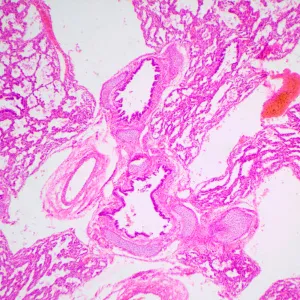

Студенческий микроскоп MAGUS Bio 240B предназначен для профессиональной подготовки. С его помощью можно проводить исследования в проходящем свете по методу светлого поля и изучать прозрачные и полупрозрачные биологические препараты. Микроскоп оснащен кодированным револьвером под 4 объектива с интеллектуальным освещением: его яркость подстраивается под каждый объектив. Прибор имеет небольшие габариты, его удобно перемещать и хранить.

- Микроскоп для исследований в проходящем свете и изучения прозрачных и полупрозрачных препаратов